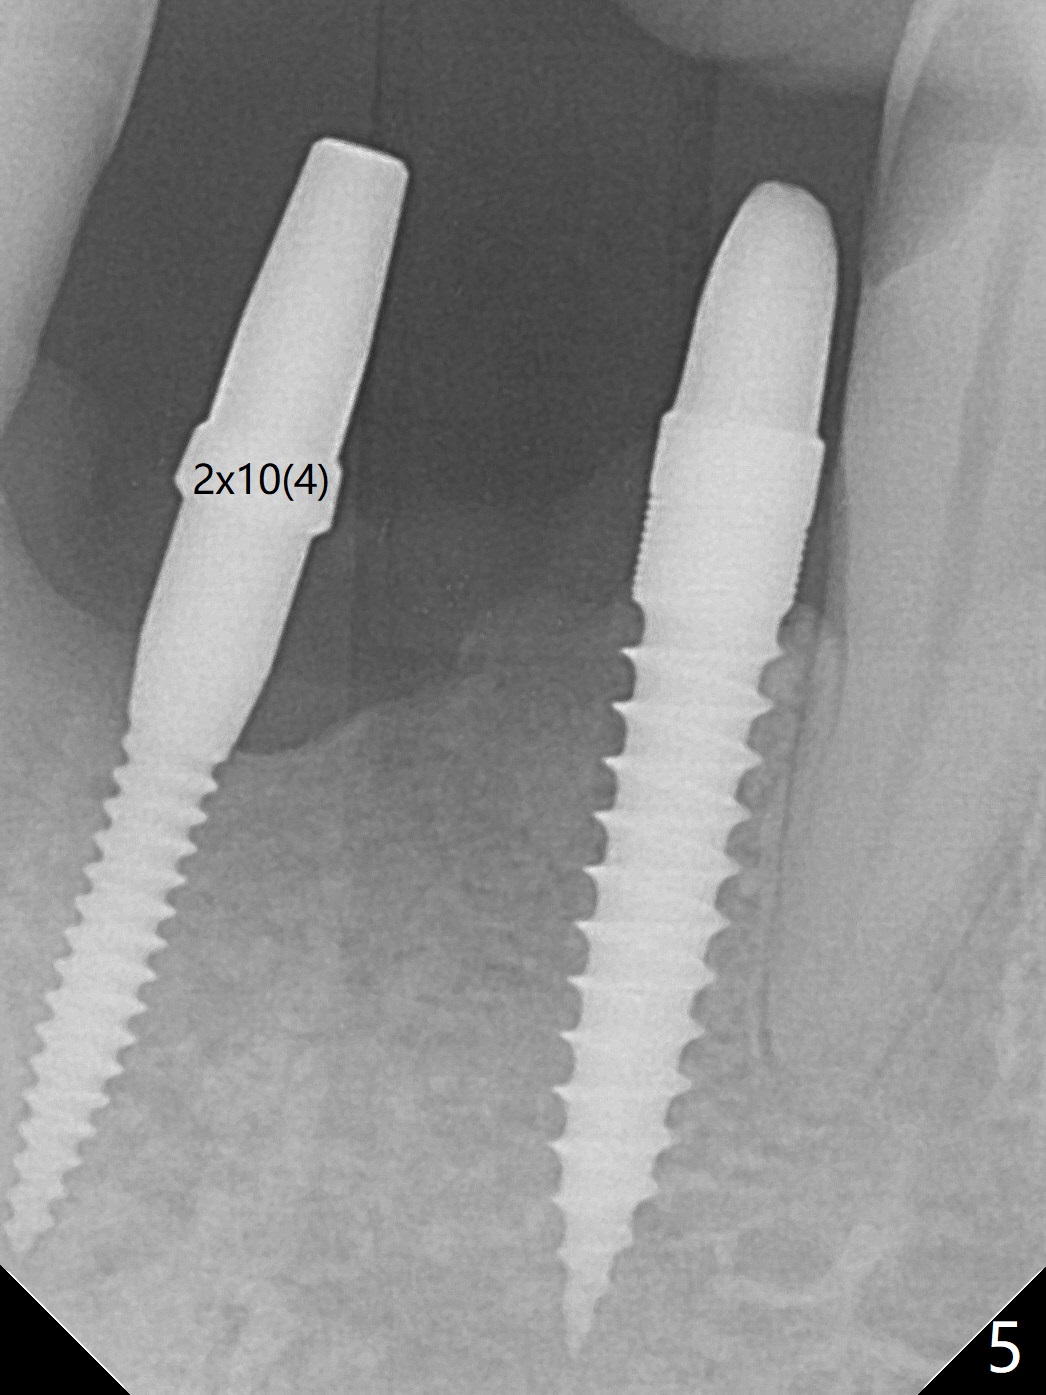

After removing #23-26 FPD and the 3x14 mm 1-piece implant at #26 (Fig.1,2 *), a new osteotomy is initiated in the narrow ridge (after ridge top reduction) approximately at #25 (Fig.2 <). Following placement a 2x10(4) mm implant at #25 (Fig.3-5) and Osteogen plug in the osteotomy at #26, Vanilla graft is placed around the implant, especially buccal. Periodontal dressing is applied after suturing. The buccal and lingual flaps are erythermatous and edematous without pain 8 days postop (Fig.6). The wound seems to be healing 2 weeks postop (Fig.7), no sign of osteonecrosis. With placement of a 2 mm implant at #25 (Fig.8 (>: bone graft buccally)), the buccal plate remains normal in thickness. When a 3 mm implant is placed at #23 (Fig.9), approximately 4 threads appear to be exposed (between arrowheads), partially due to the thick lingual plate (*).